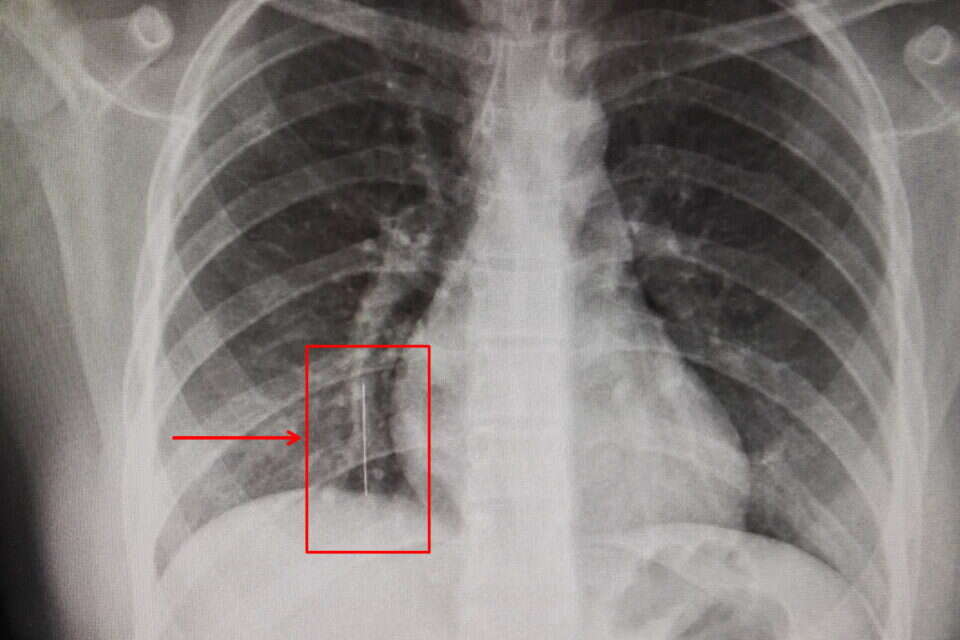

הטיול השנתי של ס' בת ה-13 תושבת הצפון הסתיים במקום הכי פחות נעים שאפשר – חדר הניתוח של המרכז הרפואי הלל יפה. "היינו באוטובוס בחזרה מטיול בטבריה, וכבר ממש ליד הבית ושוחחתי עם חברה אגב סידור של החיג'אב", שיחזרה ס', "שמתי את הסיכה בפה, כמו שאני עושה לא פעם, ובטעות בלעתי אותה". מנהל בית הספר התקשר לאביה, דיווח על המקרה וזה הבהיל אותה לחדר המיון של המרכז הרפואי הלל יפה. במרכז ביצעו בדיקות וצילום רנטגן שם הבחינו בסיכה באורך 3.6 סנטימטר היושבת בבסיס הריאות. מקום זה נחשב מסוכן במיוחד שכן הסיכה עלולה לגרום לניקוב הריאה ולקשיי נשימה קשים.

הסיכה באורך 3.5 שהוצאה מהריאה בהליך רפואי מורכב // צילום: המרכז הרפואי הלל יפה